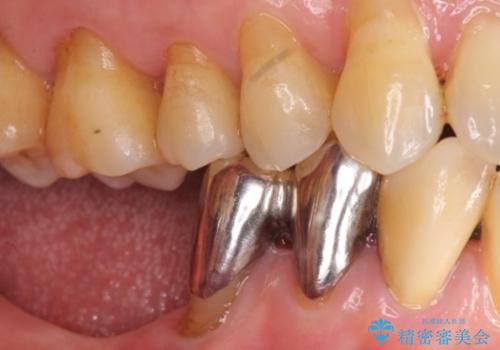

入れ歯も抵抗があるとのことから、相談を重ね、今の状態では保存不可能な下の前歯(左下2)を抜去し、ブリッジや連結補綴により動揺を抑えることにしました。

下顎大臼歯が欠損したままで今ある歯に負担がかかりやすいことから、長期的予後は保証できないことをご理解頂いた上で治療を行いました。

- ¥1,110,000 (根管治療×1本、土台×2本、仮歯×9本、クラウン×9本)費用は治療当時の料金となります